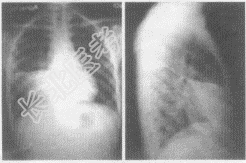

- 多项选择题2.患者行胸片正侧位检查,胸片图像表现如下, 你认为该患者应首先考虑哪些疾病

A、右肺中叶大叶性肺炎

B、右肺中叶肺癌

C、右肺中叶支气管扩张

D、右肺中叶结核

E、右肺中叶腺瘤

D、右中下肺野形成一片密度增高的阴影,与右心缘相连,其上缘锐利平直,由此向下逐渐变淡,移行至正常透亮的肺野,肋膈角清晰

E、侧位片上呈三角形,尖端指向肺门,底部紧接前胸壁或肋膈角,上缘以横裂为界,下缘为斜裂的前半部